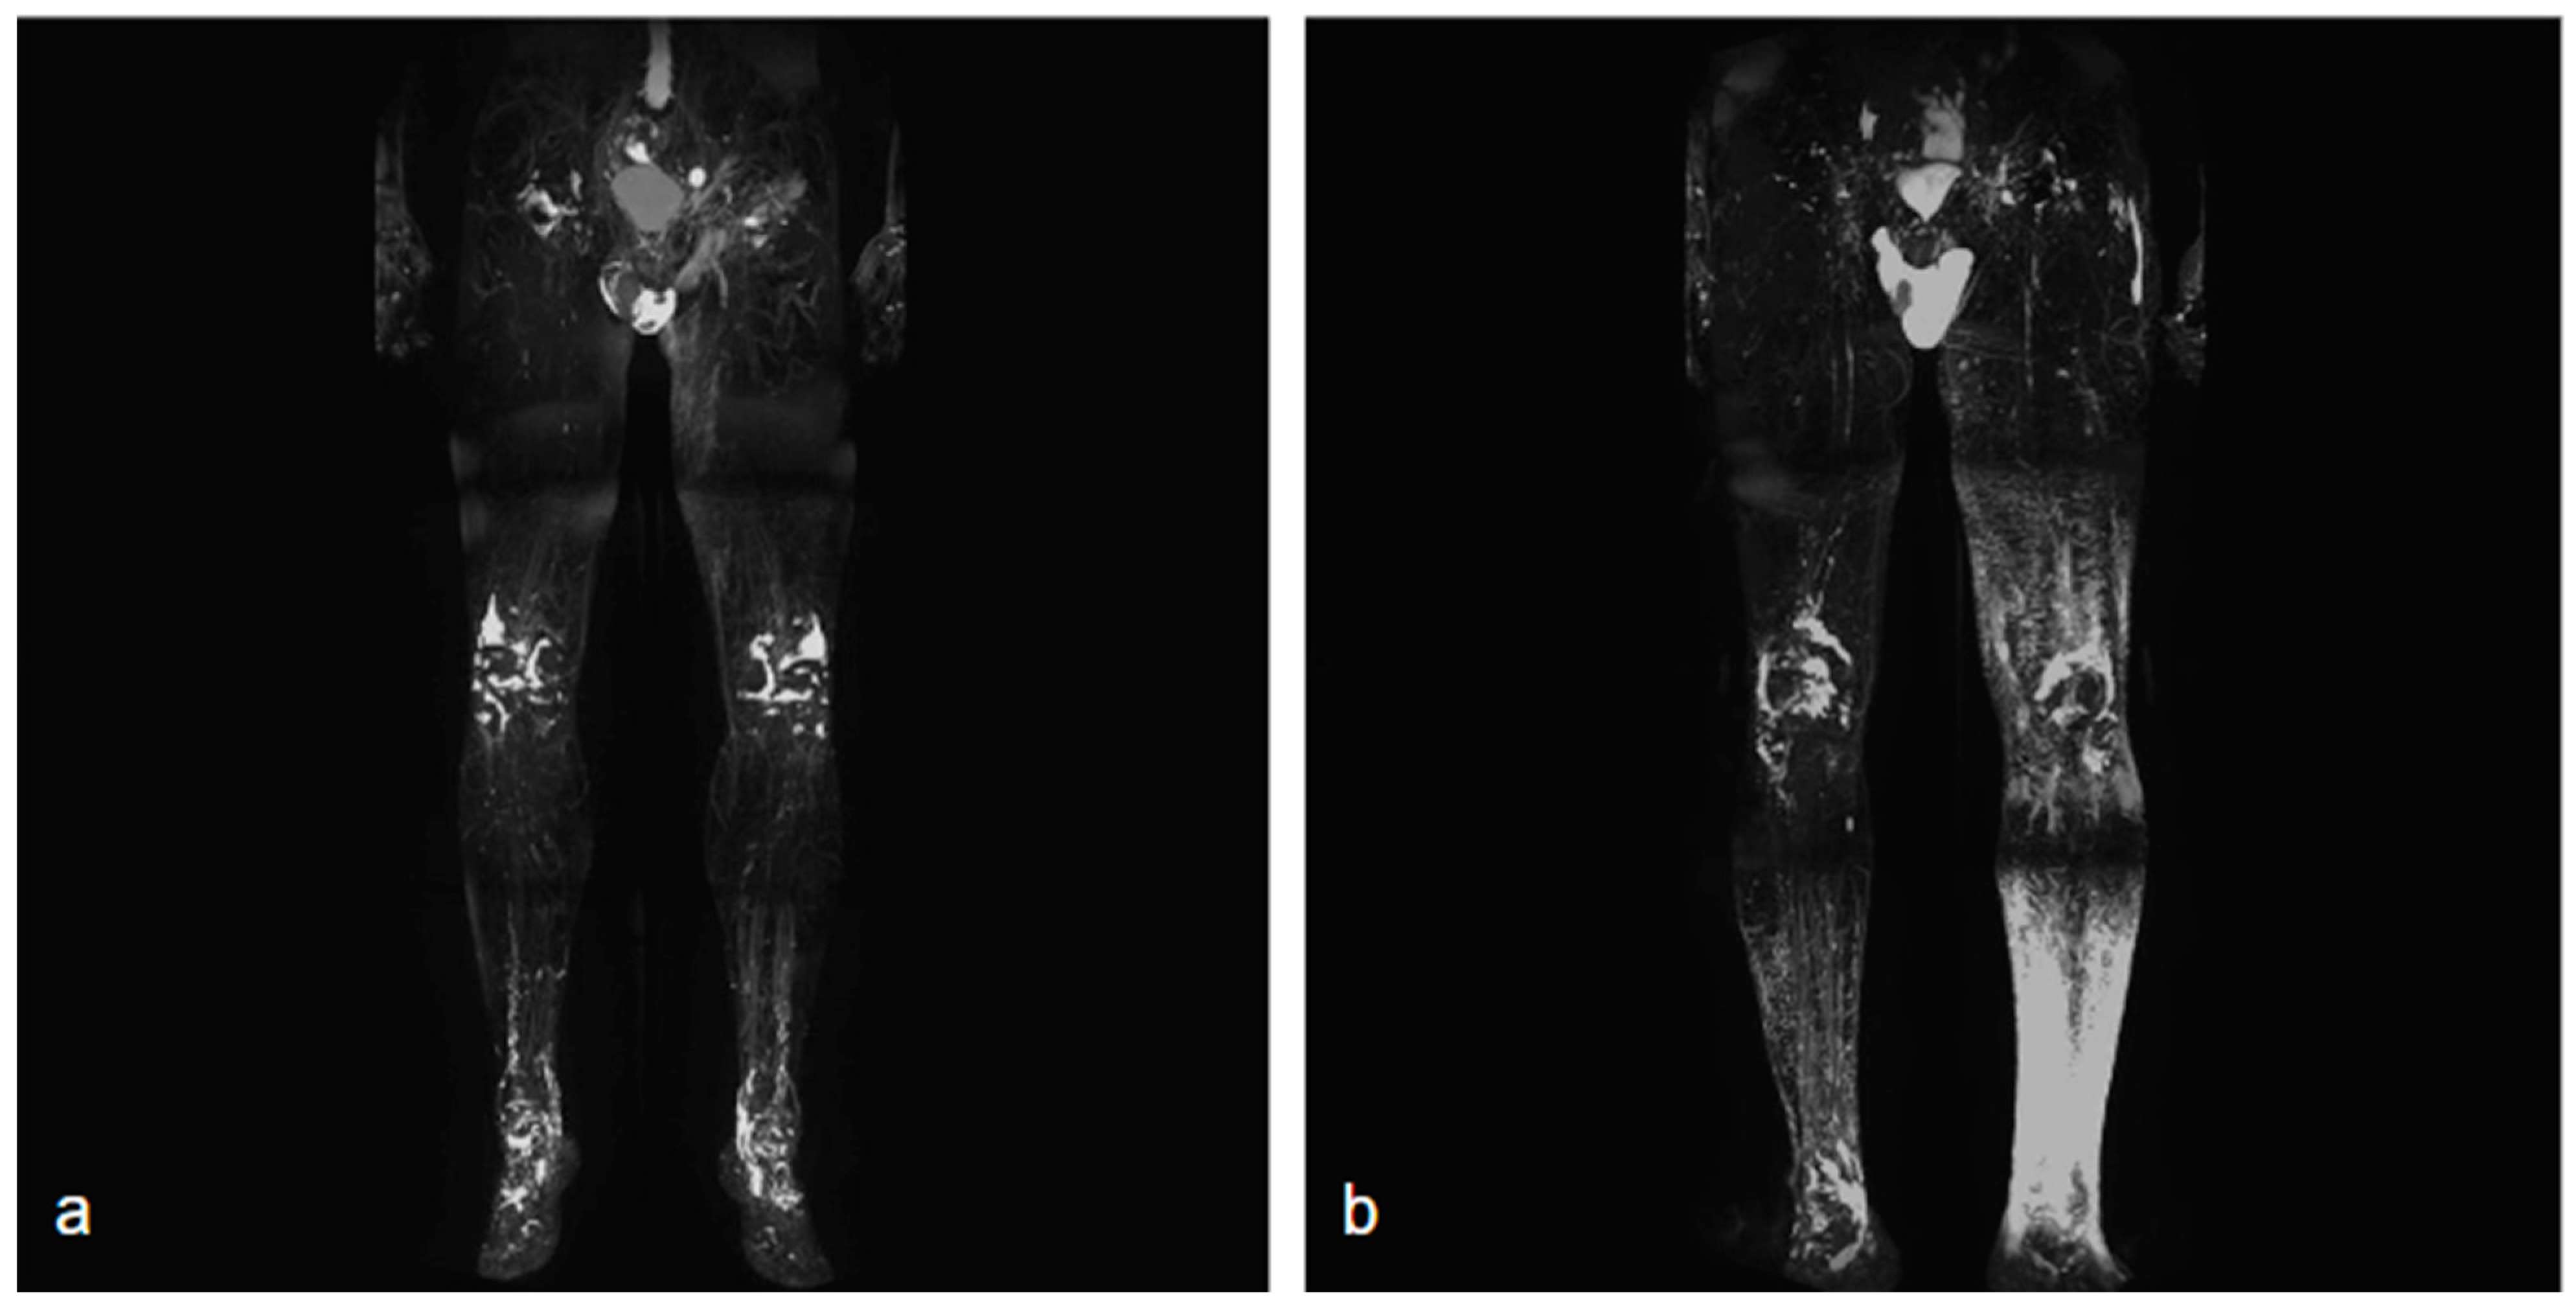

Surgical management of lymphedema is typically reserved for more severe cases and can be divided into physiological and debulking procedures. The goal of surgical treatment is to improve the functional status of patients (Figure 3).

Figure 3. Lower limb conditions 9 months post-surgery (a) compared to preoperative conditions (b) in a patient with secondary lymphedema treated with VLNT in the right knee (using right lateral thoracic flap) and BioBridge™.